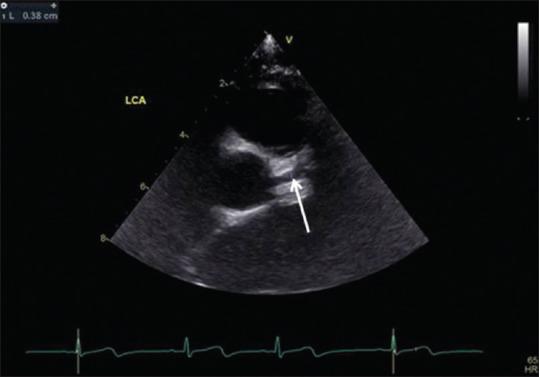

Kawasaki disease (KD) is an etiology-unknown but with a generalized inflammatory disorder of multiple organs and systems in childhood. The basic pathologic changes are panvasculitis of the small and medium-sized arteries, mainly the coronary arteries. It is now the leading cause of acquired heart disease during childhood in developed countries and has led to the early development of angina pectoris, myocardial ischemia/infarction, and even sudden cardiac death in early adulthood. Although there is no definitive diagnostic test for KD, the accurate diagnosis is dependent on the clinical presentations to meet the diagnostic criteria. Echocardiography is a well-known noninvasive tool to detect structural abnormalities and evaluation of cardiovascular function. It has been reported to detect accurately the early and late cardiovascular abnormalities, including perivascular brightness, lack of tapering, dilatation, and aneurysmal formation of coronary arteries as well as the mitral/aortic regurgitation, pericardial effusion, and myocardial functional changes in KD. In cases of incomplete form of KD and patients whose clinical manifestations did not meet the diagnostic criteria, abnormal echocardiographic findings of coronary artery may provide the assistance for early diagnosis of KD. Long-term periodic echocardiographic follow-up is the basic and essential study for patients of KD with initial coronary arterial abnormalities. Ninety nine articles that studied echocardiographic findings of KD had been reviewed and will be discussed.

川崎病(KD)是一种病因不明的儿童期多器官和系统的全身性炎症性疾病。基本病理变化是中小动脉的全血管炎,主要是冠状动脉。它现已成为发达国家儿童后天性心脏病的主要原因,并导致成年早期心绞痛、心肌缺血/梗死,甚至心源性猝死的早期发生。虽然目前尚无针对KD的确切诊断试验,但准确诊断依赖于临床表现符合诊断标准。超声心动图是一种众所周知的用于检测结构异常和评估心血管功能的非侵入性工具。据报道,它能准确检测KD早期和晚期的心血管异常,包括血管周围亮度、缺乏逐渐变细、扩张以及冠状动脉瘤形成,还有二尖瓣/主动脉反流、心包积液和心肌功能变化。在不完全型KD病例以及临床表现不符合诊断标准的患者中,冠状动脉超声心动图异常表现可为KD的早期诊断提供帮助。长期定期的超声心动图随访是初始冠状动脉异常的KD患者的基础且必要的检查。已对99篇研究KD超声心动图表现的文章进行了综述并将予以讨论。